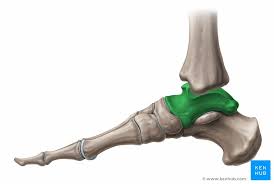

Talus Anatomie Sprunggelenke Klinik Kenhub

Den gesamten Komplex bilden außerdem Gelenke Fußwurzelgelenke Gelenke der Mittelfußknochen und Zehengelenke viele für die. Die Basen der Mittelfußknochen werden darauf mit der Fußwurzelknochenreihe mit Schrauben versorgt. Hühneraugen und Schwielen sind dicke harte Hautpartien die sich häufig an der Seite deiner Füße und Zehen entwickeln. Andere Erkrankungen der Füße entstehen durch Krankheiten die viele Bereiche des Körpers betreffen wie Diabetes mellitus Gicht oder andere Arthritisformen. Den gesamten Komplex bilden außerdem Gelenke Fußwurzelgelenke Gelenke der Mittelfußknochen und Zehengelenke viele für die. Das untere Sprunggelenk verbindet das Sprungbein mit den Knochen der Fußwurzel und dem Fersenbein. Sie unterstützen uns bei der Beantwortung der Fragen welche Seiten am beliebtesten sind welche am wenigsten genutzt werden und wie sich Besucher auf der Website bewegen. Trochanter grch der Rollhügel sd am Oberschenkelknochen. Fuß- und Knöchelbrüche sind recht häufig.